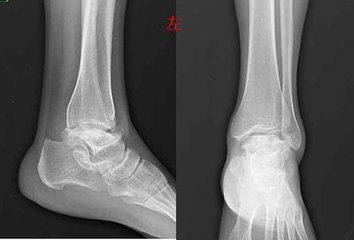

(图:治疗后的左足踝关节X光)

经过第一个疗程治疗,孙先生的双肘、双膝关节疼痛症状明显减轻很多,僵硬感基本消失,红肿有所消退,关节能缓慢转动。

经过第二个疗程治疗,孙先生的多关节处痛风石在逐渐溶解,双肘、双膝关节红肿痛现象基本消失,左足踝关节溃*处破**在慢慢好转。

经过第三个疗程治疗,孙先生的全身多关节痛风石全部溶解,没有僵硬感,左足踝关节溃烂处基本恢复正常,各个关节活动无阻。

三个月后,孙先生来院复查,全身关节痛风症状全部消失,没有任何不适感,检查报告显示尿酸值恢复到正常值,无需再治疗。